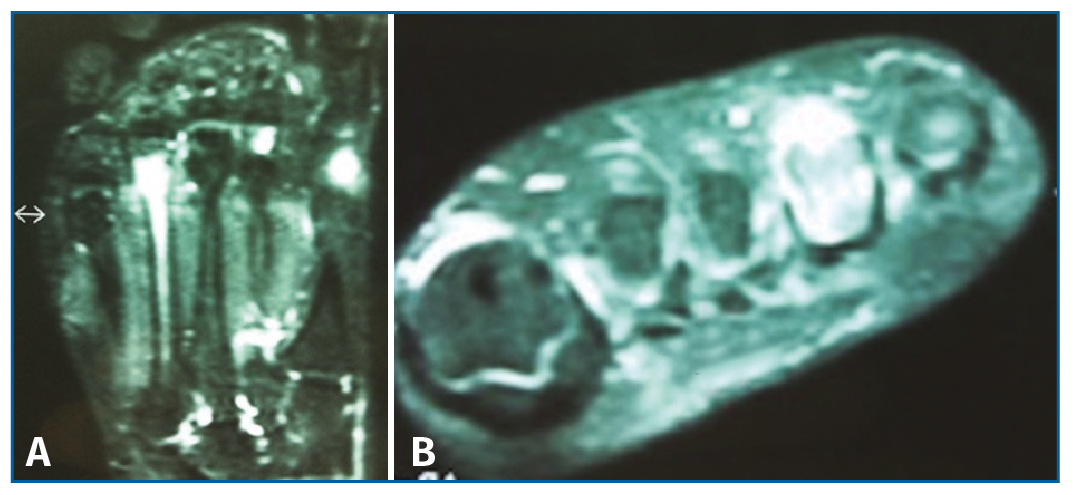

Se solicitó una resonancia magnética (RM) en dispositivo convencional de 1,5 T que no objetivó patología neurológica intermetatarsiana, pero en la que se observaba una alteración de señal localizada en la diáfisis-epífisis distal del cuarto metatarsiano, hipointensa en T1 e hiperintensa en T2, compatible con edema óseo, y que se informó como fractura de estrés (Figura 2).

Figura 2. Resonancia magnética en corte coronal (A) y axial (B) que muestra una alteración de señal hiperintensa en T2 a nivel diáfisis-epífisis del 4.º metatarsiano.